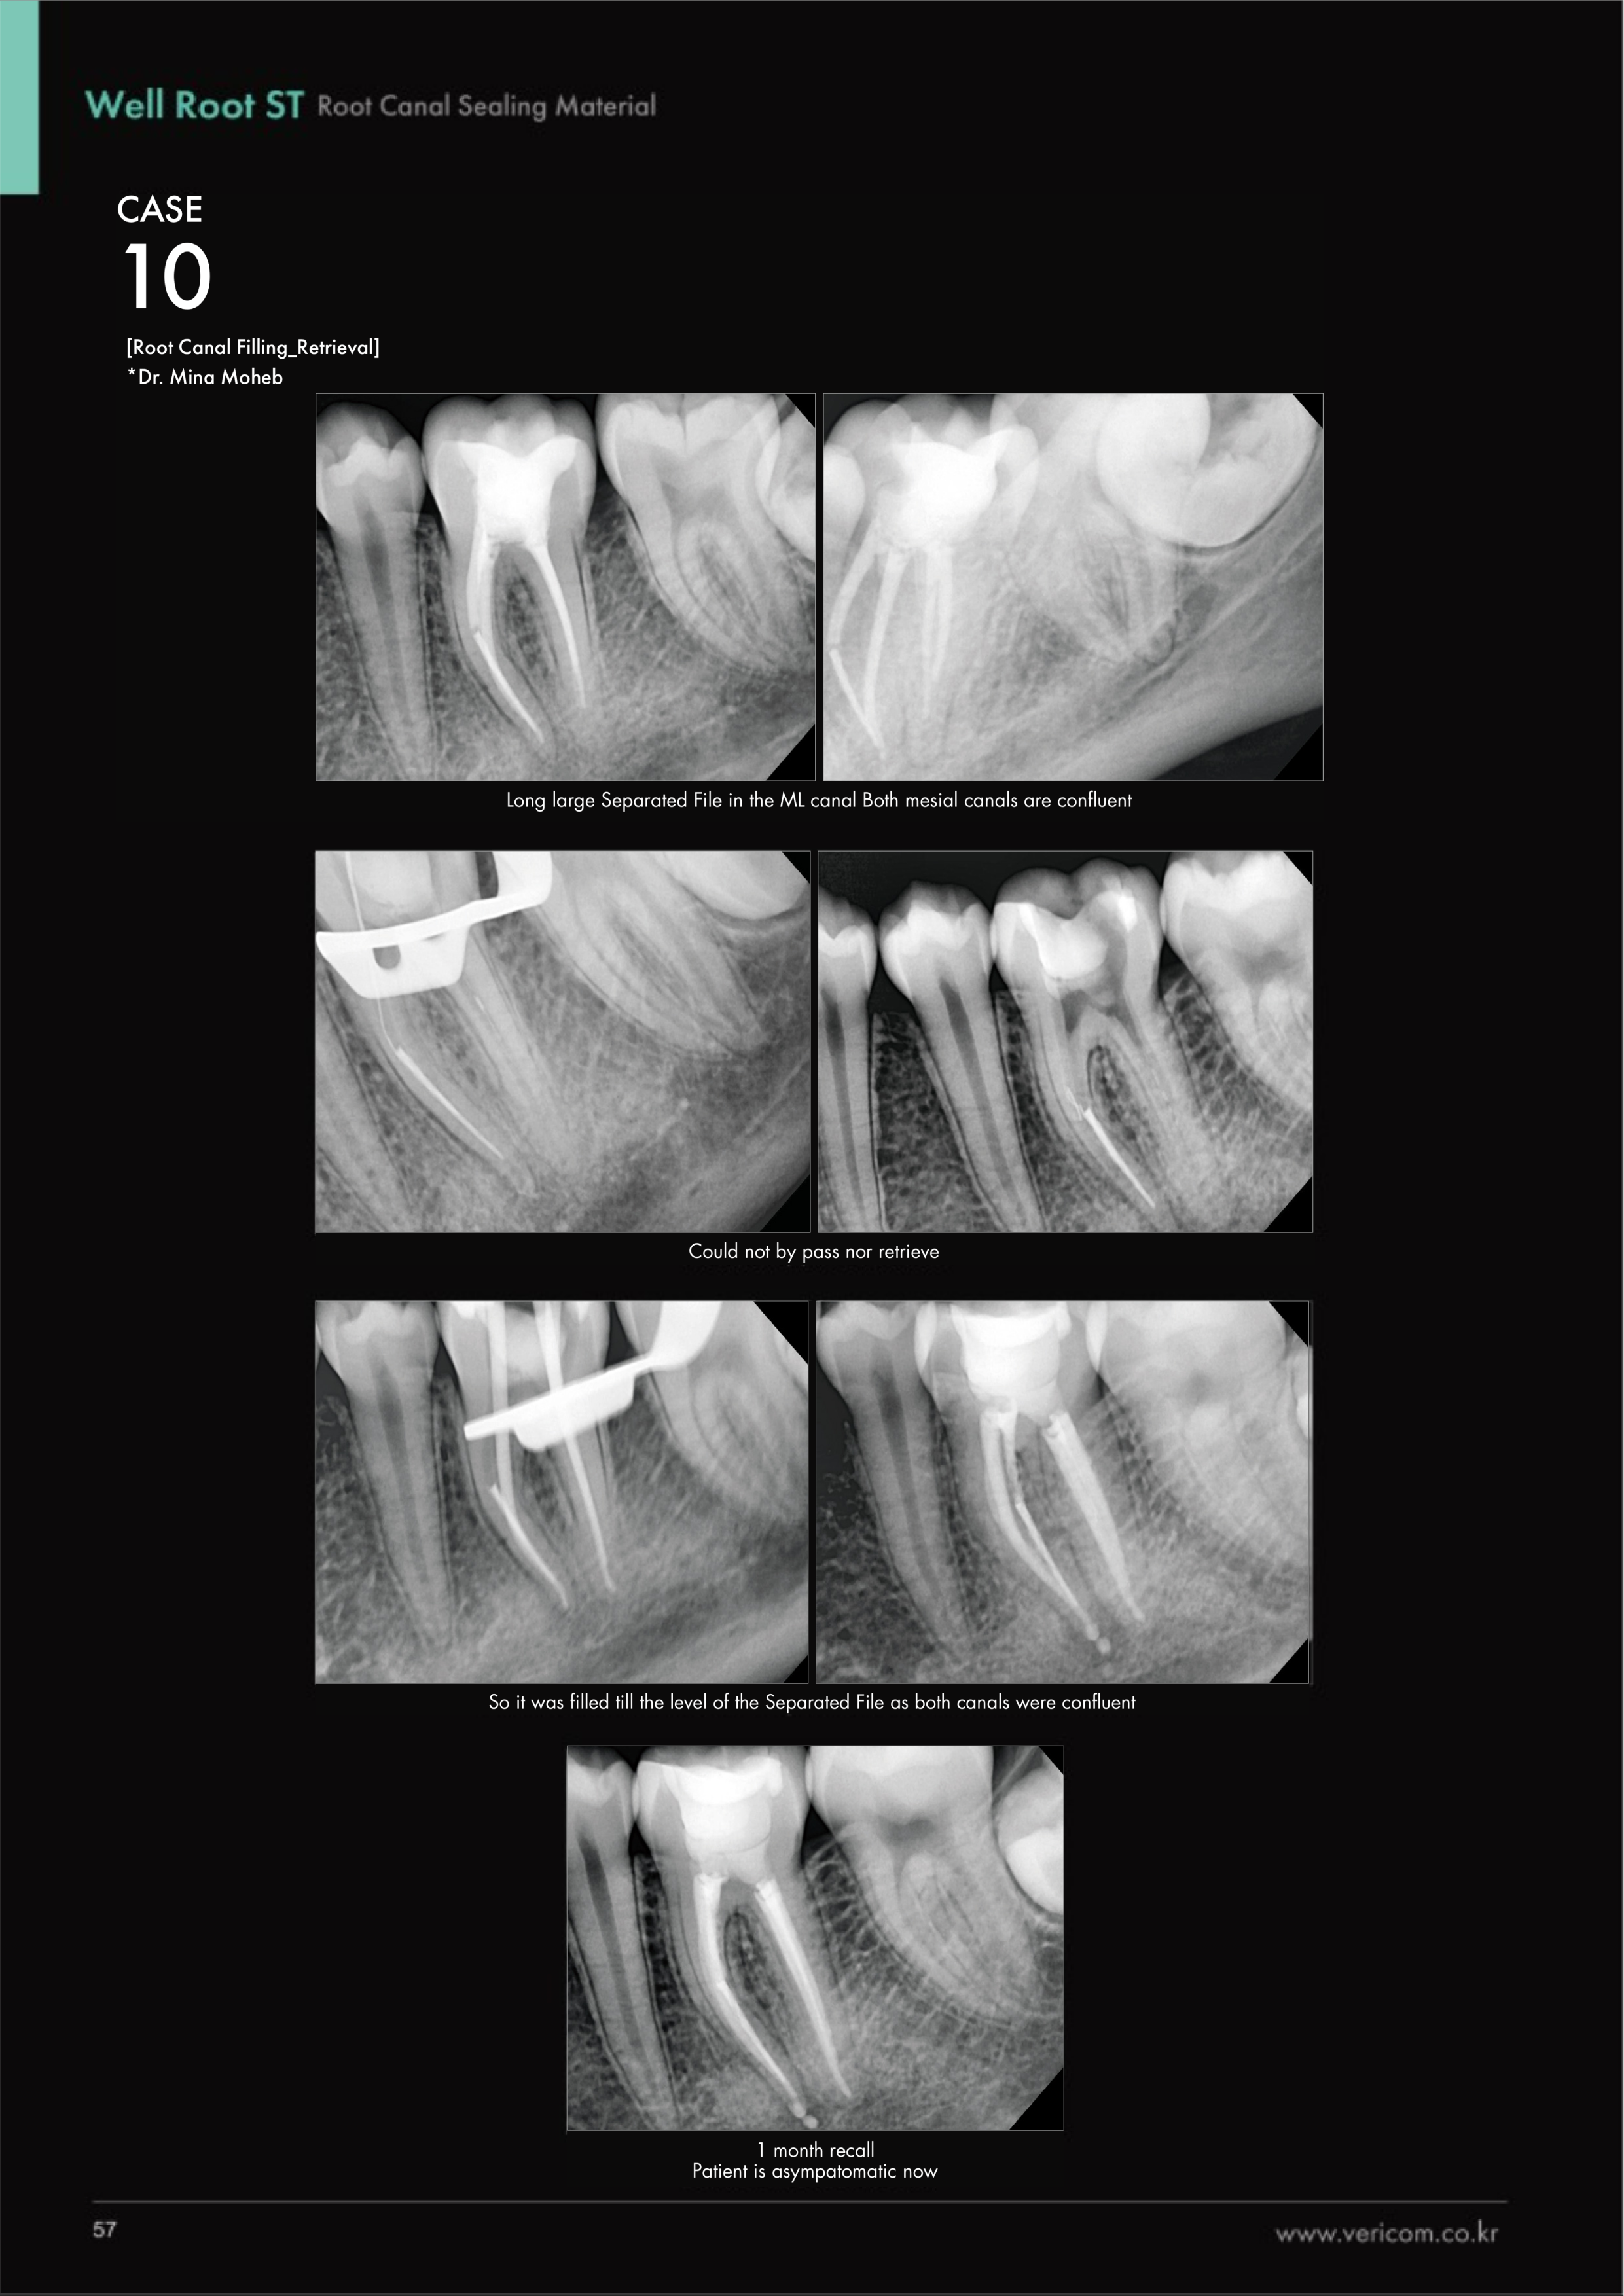

Well Root ST(GB10267123-138019)_Premixed Bioceramic Sealer